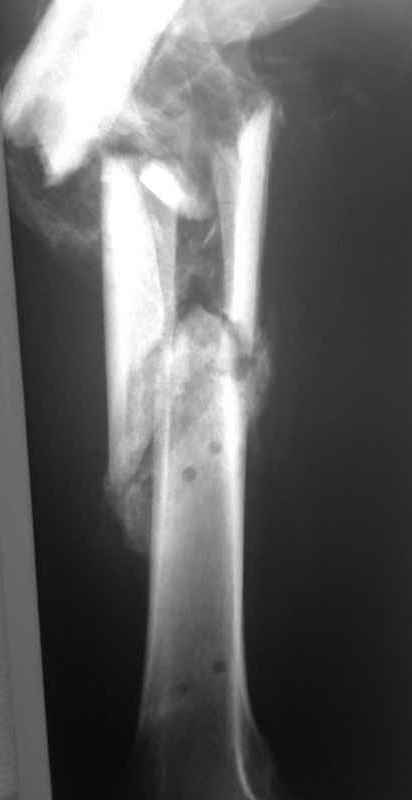

Re: Неправильно срастающийся оскольчатый перелом бедра